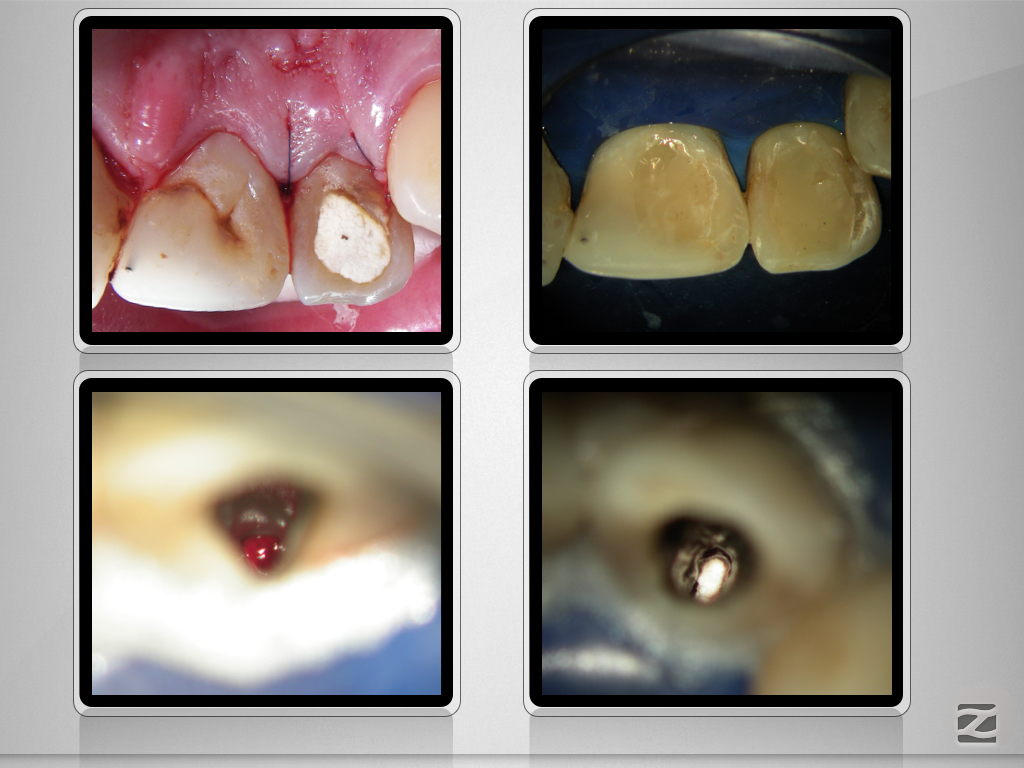

12,11 D.005

Wer hätte es gedacht , …